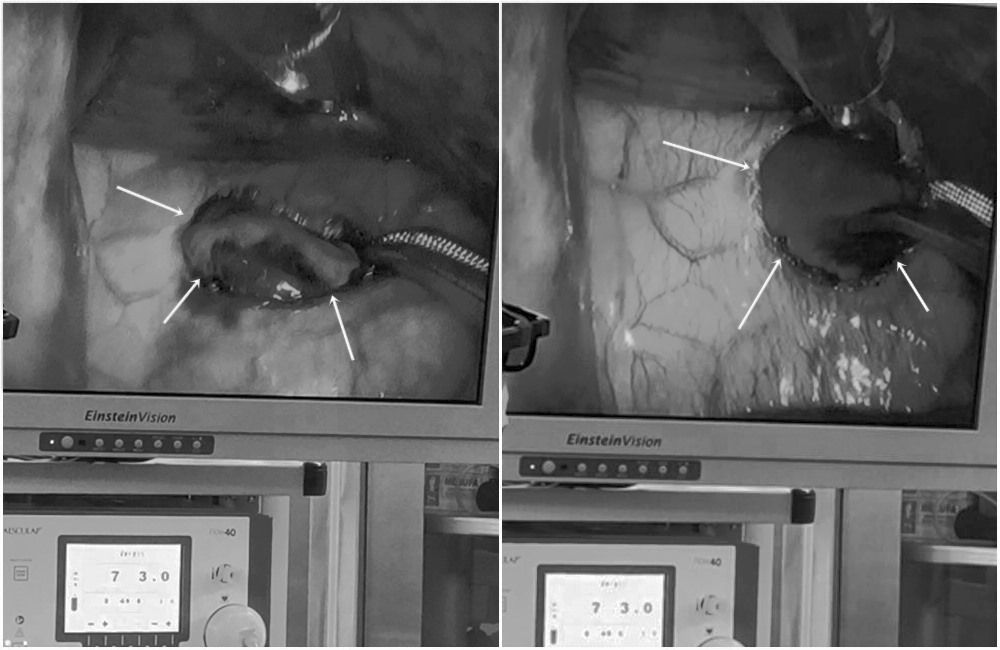

Doctors determined that this was a dangerous wound, possibly a heart wound. Emergency surgery was performed quickly. Doctors did not wait for test results but rushed him straight into the operating room to perform life-saving surgery.

MSc. Dr. Nguyen Hoang Nam - Deputy Head of Cardiovascular and Thoracic Surgery Department, Cardiovascular Center, E Hospital - said that after more than 2 hours of emergency surgery to save the patient's life, the patient's hemorrhagic shock has stabilized and he has been transferred to the Intensive Care Unit for treatment. Here, the patient is conscious and responsive, breathing oxygen on his own, and is expected to be discharged in the next few days.